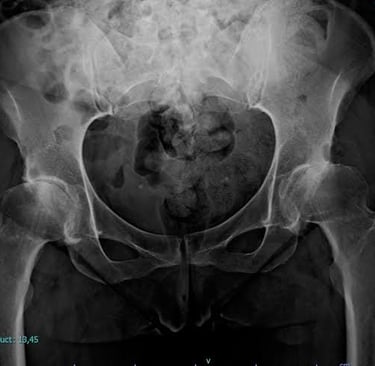

Radiografías, más utilizadas cuando el niño crece y los huesos se desarrollan más